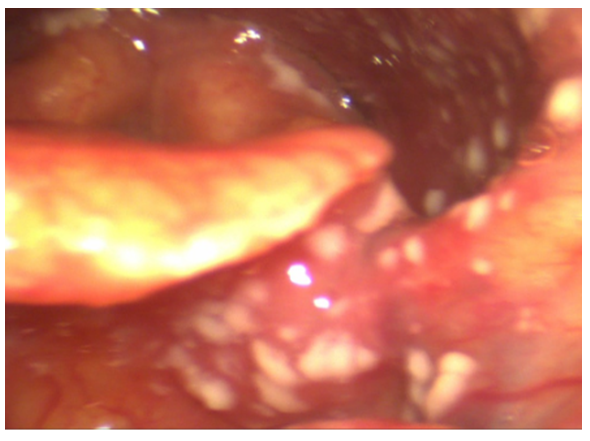

The ENT performed videoendoscopy with 0° rigid and flexible optic fibers. The findings from the videoendoscopy revealed significant abnormalities at the inner third of nasal fossae, pharynx, left tonsillar pillar, left part of soft palate, uvula, (Figure 1) epiglottis (Figure 2) but still sparing glottal and tracheal regions.

Figure 1 Mycosis involving istmus fauci, from left amygdala till soft palate and uvula.